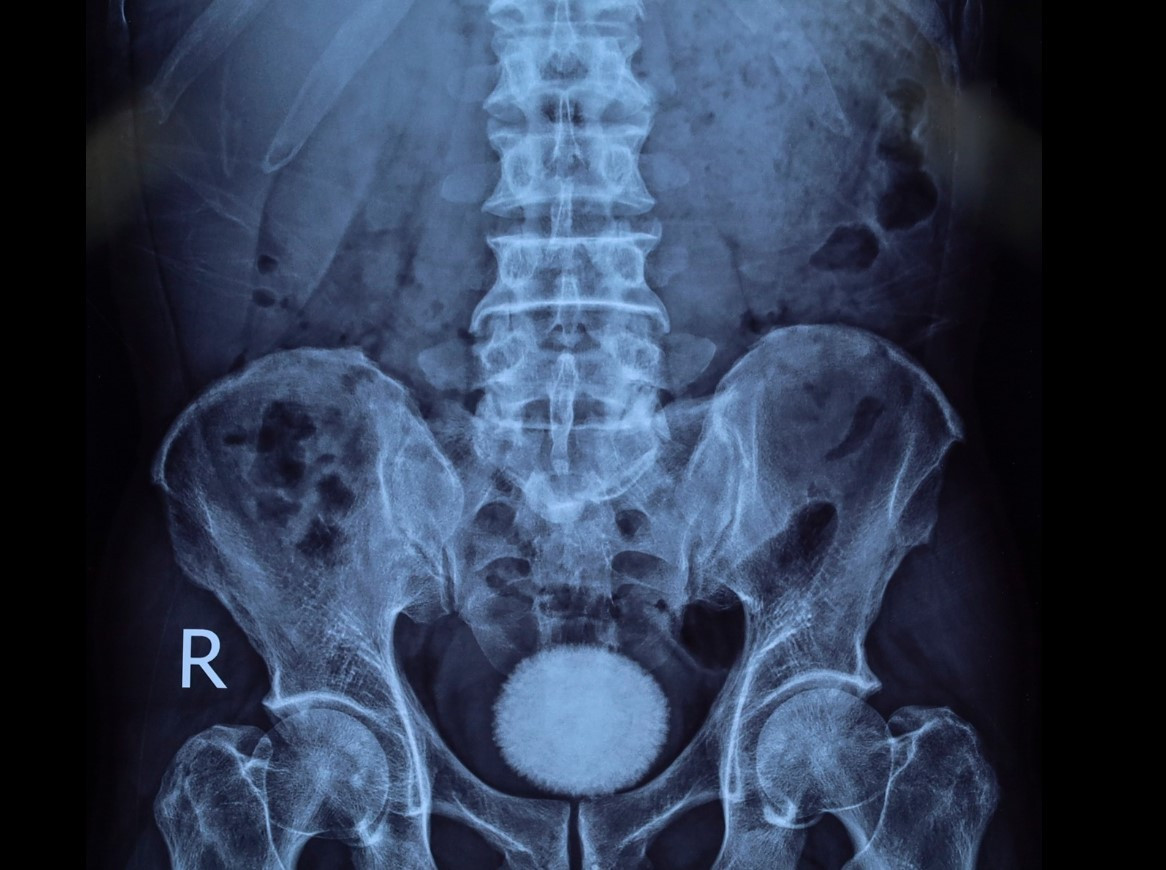

Trên siêu âm và chụp X-quang đều cho hình ảnh sỏi bàng quang kích thước lớn 60x40 mm. Vì vậy, các bác sĩ đã chỉ định người bệnh phẫu thuật lấy sỏi bàng quang.

soi-bang-quang-2.jpg

Viên sỏi bàng quang trên phim chụp - Ảnh BVCC

Trong quá trình phẫu thuật, ê-kíp tiến hành rạch da đường giữa trên xương mu, tiếp cận bàng quang và lấy ra một viên sỏi lớn có kích thước và hình dáng như trên phim, lớn như một quả trứng ngỗng. Sau đó bàng quang được bơm rửa sạch và khâu phục hồi theo đúng quy trình chuyên môn.